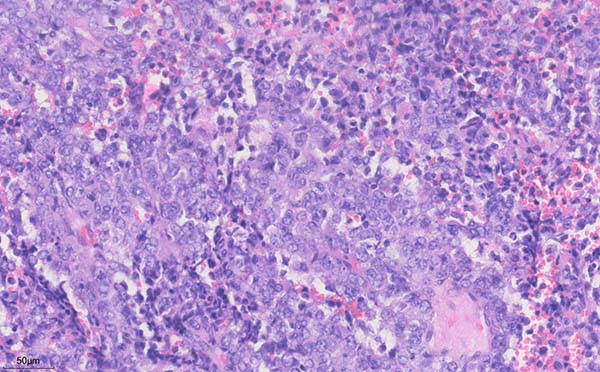

细胞沉渣石蜡包埋HE切片:血性背景中可见大量恶性肿瘤细胞,粘附性差,核形不规则,可见泡状核,部分胞浆丰富,核分裂象易见。

细胞沉渣免疫组化显示肿瘤细胞:TTF-1(-),Napsin-A(-),EMA(+),Calretinin(间皮+),Desmin(间皮+),CK7(间皮+),CK5(间皮+),CK(间皮+),Vimentin(+),LCA(淋巴细胞+),CgA(个别+),INI1(+),BRG1(部分-,部分弱+),BRM(-),WT-1(间皮+),Syn(+),CD56(-)。

(胸水)细胞沉渣石蜡包埋HE切片病理诊断:可见恶性肿瘤细胞,分化较差,免疫组化结果提示BRG1蛋白表达显著降低、BRM蛋白表达缺失,伴有神经内分泌表达,符合SMARCA4缺失型未分化肿瘤。